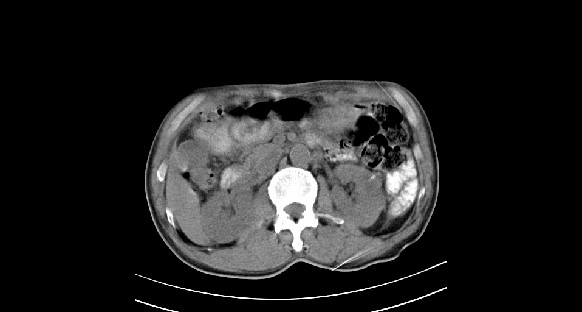

男性,70岁,体检b超发现左肾占位,请各位战友发表一下观点

左肾有两个病灶,且较大的病灶内可见点状钙化灶,增强扫描边缘也是呈渐进性强化,中央部分未见明显强化